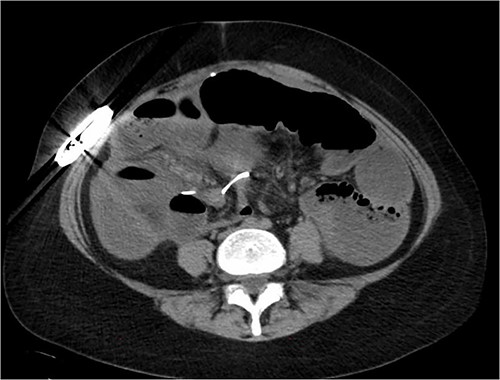

Our patient was a 38-year-old woman with a history of systemic lupus erythematosus (SLE) who underwent an uneventful open gastric stimulator placement for idiopathic gastroparesis. Past surgical history was significant for a total colectomy with ileo-rectal anastomosis for lupus colitis and she was on oral steroids for SLE at the time of the pacemaker insertion. Three months later, she presented with complaints of frequent flipping of the battery in the subcutaneous pocket and underwent a revision of the pocket. One month after this pocket revision (4 months after the initial placement of the pacemaker), she presented to ER with acute abdominal pain for 3 days associated with nausea and vomiting. On physical examination, her abdomen was tender to palpation over the epigastrium with guarding. Laboratory studies revealed a very low white-cell count of 1118 per cubic millimeter (normal 4000–11 000) and an elevated serum lactate level of 5.6 mmol per liter (normal 0.5–2.2). CT revealed diffuse bowel dilation with thickening, mesenteric fat stranding and air-fluid levels and the gastric pacemaker wires appeared wrapped around the small bowel mesentery (Fig. 1). She became acutely hypotensive and required fluid resuscitation and vasopressors. Patient underwent emergency laparotomy after initial fluid resuscitation. A long segment of the ileum was noted to be ischemic secondary to the gastric stimulator wires forming a 360-degree loop around the base of the mesentery (Fig. 2). Gangrenous bowel was resected starting from a point 150 cm distal to the ligament of Treitz all the way to her ileo-rectal anastomosis. A total of 140 cm long segment of distal small bowel was resected and the gastric stimulator was explanted. Patient’s small bowel was left in discontinuity. She was taken back to the OR 48 h later for a second look where the bowel looked healthy and a hand sewn anastomosis was performed between the small bowel and the rectal stump. Patient was left with a total length of 150 cm of small bowel that was connected to the rectum. Patient had an uneventful recovery and was discharged from the hospital. Over the next 2 years, patient went on to develop signs and symptoms of short gut syndrome that failed medical management. She is currently being worked up for a small bowel transplant.

CT image showing dilated small bowel with gastric stimulator wire seen looping around one of the small bowel loops suggesting possible strangulation.